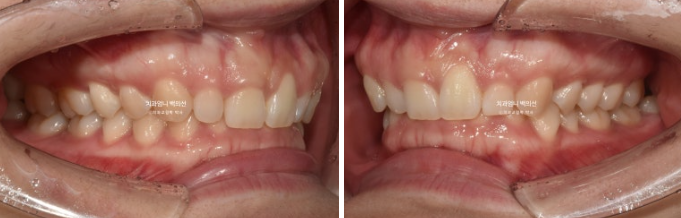

23년 4월에 거미스마일 옥니 과개교합 개선을 위해 내원하신 환자분입니다.

윗니에 덮여 아랫니가 전혀 보이지 않는 심한 과개교합 입니다.

좌우 잇몸의 높이가 다른 잇몸 비대칭도 보입니다.

앞니가 뒤로 쓰러진 옥니이고

앞니가 옥니로 뒤로 쓰러져 있으면 앞니 뿌리 잇몸이 상대적으로 튀어나와 보이게 되며 잇몸돌출처럼 보이게 됩니다.